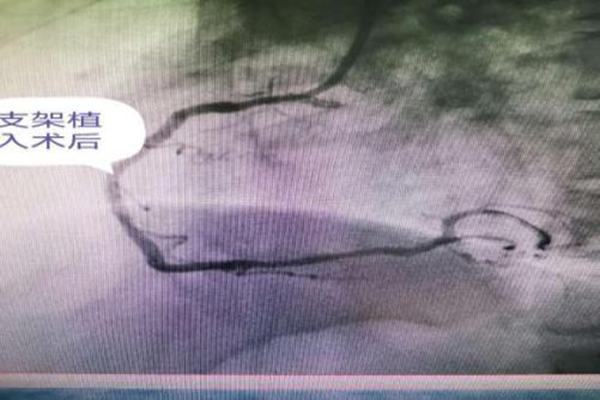

729日早6點(diǎn)起床后胸痛再次發(fā)作,服“速效救心丸也無(wú)緩解。急忙撥打我院120救治,急救醫(yī)生查心電圖示急性下壁心肌梗死,生命垂危,立即上傳我院胸痛中心,醫(yī)護(hù)人員經(jīng)胸痛綠色通道迅速將先生送入導(dǎo)管介入手術(shù)室開(kāi)始搶救。心內(nèi)科郭應(yīng)先主任和許慶華副主任憑借精準(zhǔn)判斷,迅速找到患者的罪犯血管”——右冠狀動(dòng)脈中段閉塞,迅速入一枚支架及時(shí)開(kāi)通先生閉塞的心臟血管。術(shù)中一波三折,球囊擴(kuò)張后出現(xiàn)無(wú)復(fù)流,患者胸痛劇烈,立即給于冠脈內(nèi)溶栓治療,刺破球囊送至病變遠(yuǎn)端造影示病變處出現(xiàn)夾層,立即植入支架,造影示血流恢復(fù),患者胸痛迅速緩解。患者生命體征平穩(wěn)轉(zhuǎn)入了監(jiān)護(hù)病房繼續(xù)治療

右冠中段次全閉塞

支架植入術(shù)后